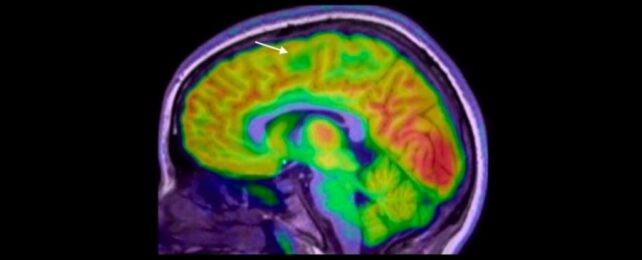

L’épilepsie a plusieurs causes, et environ trois cas sur dix proviennent d’anomalies structurelles du cerveau. Ces lésions passent souvent inaperçues sur les IRM — surtout les plus petites —, parfois cachées au fond d’un pli cérébral. L’étude a été dirigée par Emma Macdonald-Laurs, pédiatre neurologue au Royal Children's Hospital de Melbourne, qui explique que l’IA peut aider à repérer ces éléments et accélérer les décisions de traitement.

Les chercheurs ont entraîné l’IA sur des images du cerveau d’enfants pour trouver des lésions de la taille d’une myrtille ou moins. En combinant l’IRM et une autre technique appelée PET, le taux de réussite était de 94% dans un groupe et 91% dans l’autre. Sur 17 enfants du premier groupe, 12 ont subi une chirurgie pour enlever les lésions et 11 sont aujourd’hui sans crises.

80% des patients avaient préalablement eu une IRM normale. L’outil n’enlève pas le rôle des radiologues ou des médecins; c’est un détective qui aide à assembler les pièces du puzzle pour proposer une chirurgie potentiellement salvatrice. « Le tool ne remplace pas les radiologues ou les médecins de l’épilepsie, mais c’est comme un détective qui nous aide à mettre les pièces du puzzle ensemble plus rapidement afin d’offrir une chirurgie potentiellement salvatrice, » précise l’équipe. Des experts de King’s College London réagissent: « Ce travail est vraiment excitant et les résultats sont vraiment impressionnants. » Cependant, le physicien Konrad Wagstyl rappelle que le PET est coûteux et moins accessible que l’IRM et qu’il implique une dose de radiation.